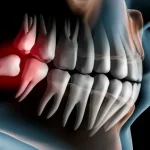

دندانپزشکی فردا یکی از مجهز ترین کلینیک های دندانپزشکی در ایران است که کلیه خدمات عمومی و تخصصی دندانپزشکی را با بهره گیری از پیشرفته ترین تجهیزات و بالاترین استاندارد های دنیا در اختیار مراجعین قرار می دهد.کلینیک دندانپزشکی فردا ارائه کننده کلیه خدمات عمومی و تخصصی دندانپزشکی شامل : ترمیمی و زیبایی، درمان ریشه، دندانپزشکی اطفال، جراحی، پریو، پروتز، ایمپلنت و ارتودنسی ، با جدیدترین تکنولوژی و متد روز دنیا می باشد.

شکستگی فک یا اوفتادن دندان